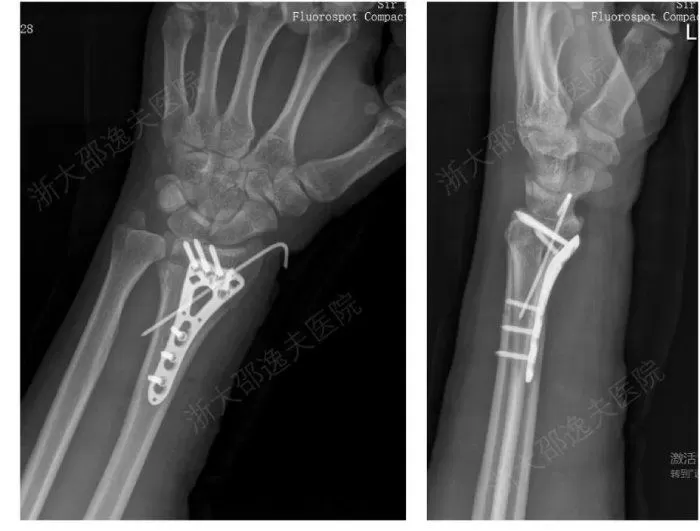

인사이트연구진이 '본-02'로 골절을 치료한 모습 / CCTV

실제 임상 사례에서는 손목 골절 환자에게 3cm 정도의 작은 절개만으로 접착제를 주입한 후 3분 만에 골절 부위가 고정됐습니다.

기존 치료법이었다면 이 환자는 금속판과 나사를 이용한 수술을 받고, 나사를 제거하기 위해 다음 해에 추가 수술을 받아야 하지만, '본-02'를 사용한 후 3개월간의 추적 관찰 결과 환자의 골절은 합병증 없이 완전히 회복된 것으로 나타났습니다.

인사이트기존 금속 임플란트로 골절을 치료하는 모습 / CCTV